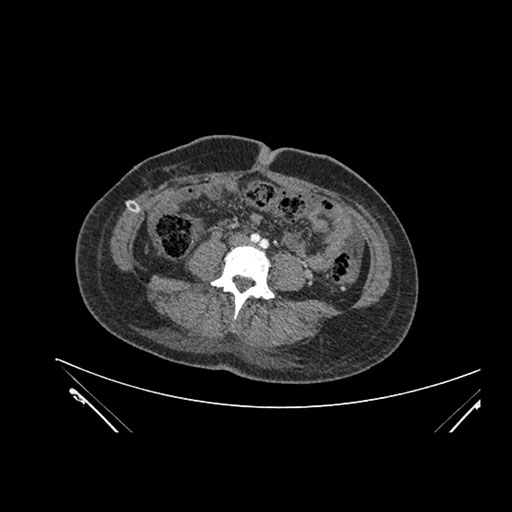

Imaging Analysis

Look through the patient's CT scan to identify any areas of concern for the necessary procedure.

Axial Venous